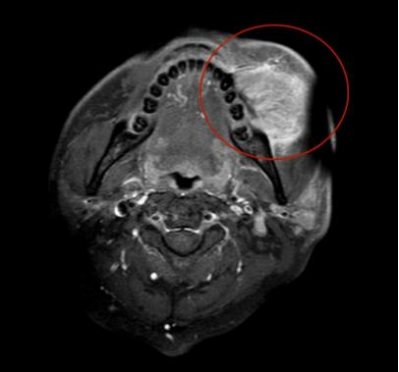

磁共振影像显示左颊部团块状肿物大小达48×39×52mm(比高尔夫球大)